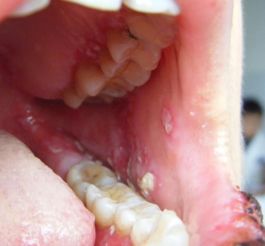

2. 黏膜表现:口腔黏膜是最常见的受累部位,表现为白色网状或花边状条纹(称为Wickham纹),可伴糜烂、疼痛或灼热感。少数患者可能累及生殖器黏膜。